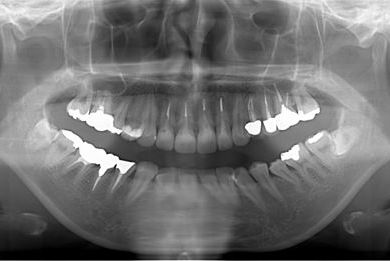

| 性別/年齢 | 女性 / 27歳 | ||||||||||||||||||||||||||||||||

| 主訴 | 審美歯科治療を希望。歯ならびもできるかぎりそろえたい。 | ||||||||||||||||||||||||||||||||

| 治療内容 | オールセラミック4本(オールセラミック用土台4本)、メタルボンドセラミック2本(メタルボンドセラミック用土台2本) | ||||||||||||||||||||||||||||||||

| 総治療費 | 867,825円 | ||||||||||||||||||||||||||||||||

| 治療期間 | 5ヶ月 |